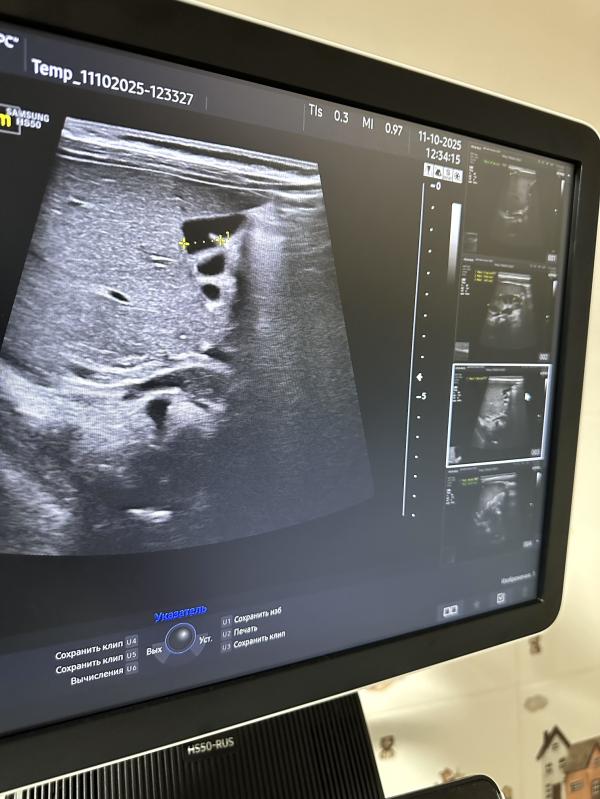

Желчный пузырь — небольшой мешочек, расположенный под печенью, предназначенный для хранения жёлчи, вырабатываемой печенью. Форма желчного пузыря обычно грушевидная, овальная или округлая. Иногда форма может меняться, приобретая перегибы, перетяжки или дополнительные складки. Такое явление называют деформацией желчного пузыря.

- Перегиб шейки желчного пузыря;

- Изгиб дна или тела пузыря;

*на сканах представлены разные желчные пузыри

Пока в просвете желчного пузыря отсутствуют признаки патологических изменений, таких как наличие желчи, конкрементов (камней) или новообразований, поводов для беспокойства нет